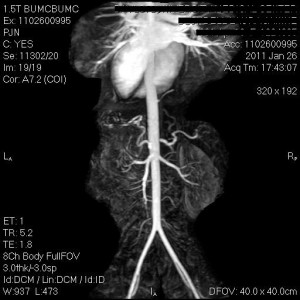

As far as I am go, I saw my cardiologist about 2 weeks ago and we switched my medications again in hopes that the new meds will keep me from having the episodes of chest pain. She has diagnosed me with coronary artery spasms, that basically do what is sounds like…my coronary arteries spasm. This leads to a decreased amount of oxygen getting to my heart and that causes the severe chest pain. So basically I take this new medication everyday and if I do have an episode I am to use my nitroglycerin and I go to the ER for pain medication if the pain just gets too unbearable. The pain meds don’t do anything to stop the spasms but it masks the pain and I can tolerate it until the spasms stop. The episodes usually last anywhere from an hour to 3 hours and are horrible! I go to bed at night praying I don’t wake up in severe pain. I feel like I’m 80 yrs old when I’m standing in line at the pharmacy getting my nitro filled. I have had one episode since starting the new medication and I’ll go back and see my cardio on Monday. Not sure what she’ll do so we’ll see. Last week, she did want to make sure nothing else was going on so we did a gallbladder ultrasound and a cardiac MRI and MRA (angiogram), both of which came back ok. Here is an awesome picture from my MRA to show you. I think it’s awesome, anyway!

I told you it was awesome….the technology these days is great!